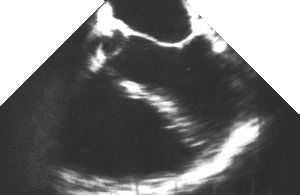

3. The LV short axis mitral view (TG Basal SAX)

4. UP transgastric view of mitral valve CLICK FOR VIDEO: transgastric view of mitral valve

Again, move your mouse cursor over the left image to reveal the labels. The anterior leaflet of the mitral valve (aml) is clearly seen between the left ventricular outflow tract (lvot) and the mitral valve orifice (mvo).